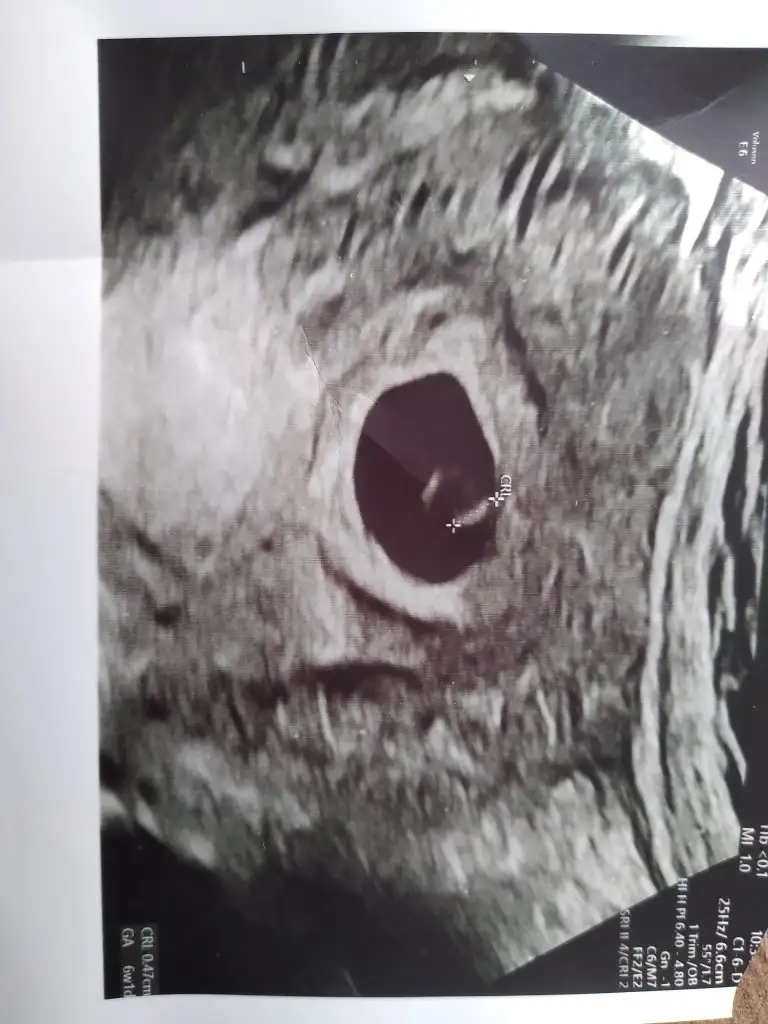

Merhaba 6+5 çift yumurta ikizleri (iki ultrasonda ayrı )vajinal muayane 3. Fotoda iki kese görünüyor